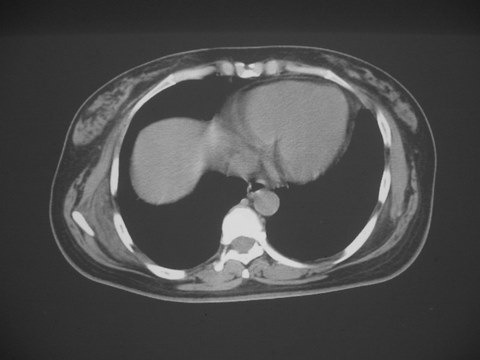

无意中发现右背部肩胛下缘半球状突起,无红,热,痛感觉。拍平片未见异常。ct发现右肩胛下角深层新月型软组织肿胀,ct值-50至15,大家看看是什么性质,来源,初步考虑来源于下后锯肿,考虑下后锯肌肿胀,可是病人无明确外伤史,也不疼痛

典型位于背部,在肩胛下角和胸壁软组织之间,肿瘤表面为菱形肌和背阔肌所被覆深部,紧邻肋骨和肋间肌,呈半圆形或扁豆状,宽基底与胸壁相交,边界比较清楚,相邻的肌肉和肋骨无侵蚀,部分病变与其表面的临近肌肉之间可受压呈弧形的脂肪界面,肿瘤周围软组织无水肿。

从mr表现可以推断ct影像,即肿块呈软组织密度,病灶内可出现脂肪密度的低密度影。